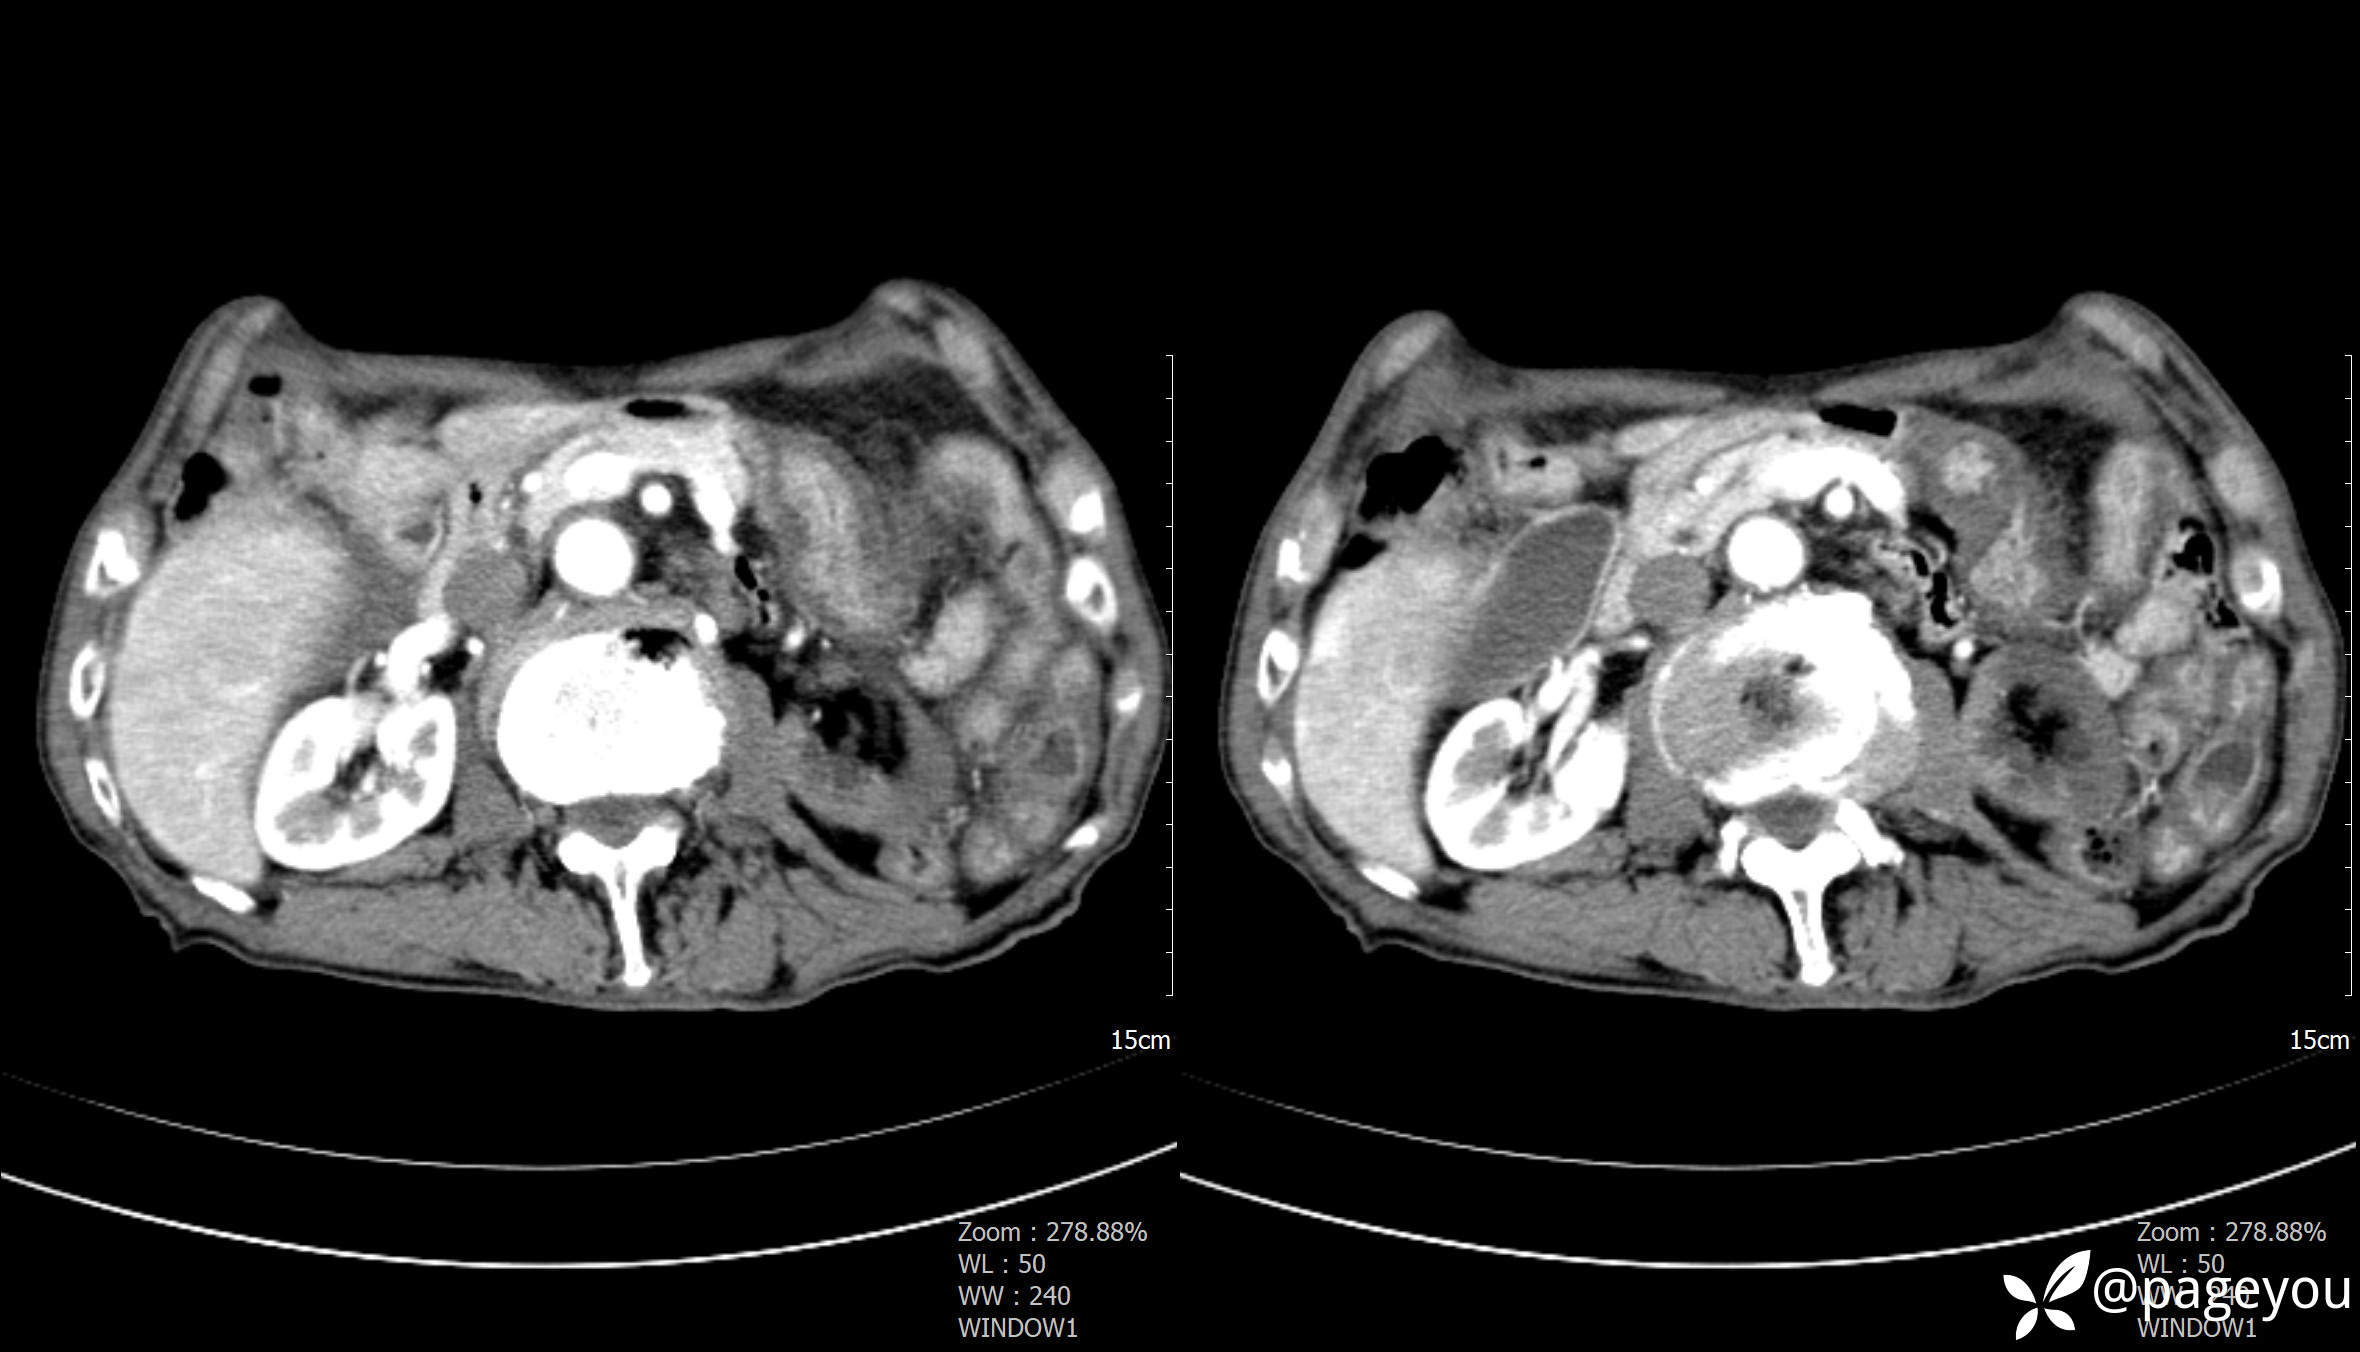

主动脉CTA: